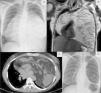

A 39-year-old Caucasian woman, former smoker (6 pack-years), was referred to the outpatient clinic with an abnormal chest X-ray that revealed a large opacity obscuring the heart border (silhouette sign), as shown in Fig. 1. Chest tomography was performed and showed a large mass occupying much of the thoracic cavity. Histological evaluation of the lesion revealed findings that suggested a thymoma. Magnetic resonance imaging revealed no invasion of neighbouring structures. The patient underwent a bilateral thoracotomy, with excision of a 3.9kg thymolipoma. The chest X-ray performed after the surgery, as shown in the image, revealed complete expansion of both lungs.

Fig. 1.

(A) Chest X-ray (posteroanterior) revealed a large opacity obscuring the heart border (silhouette sign). (B and C) Chest MRI and CT showing a large heterogeneous mass overlying the heart. (D) Chest X-ray (posteroanterior) after surgical excision showing lung expansion.